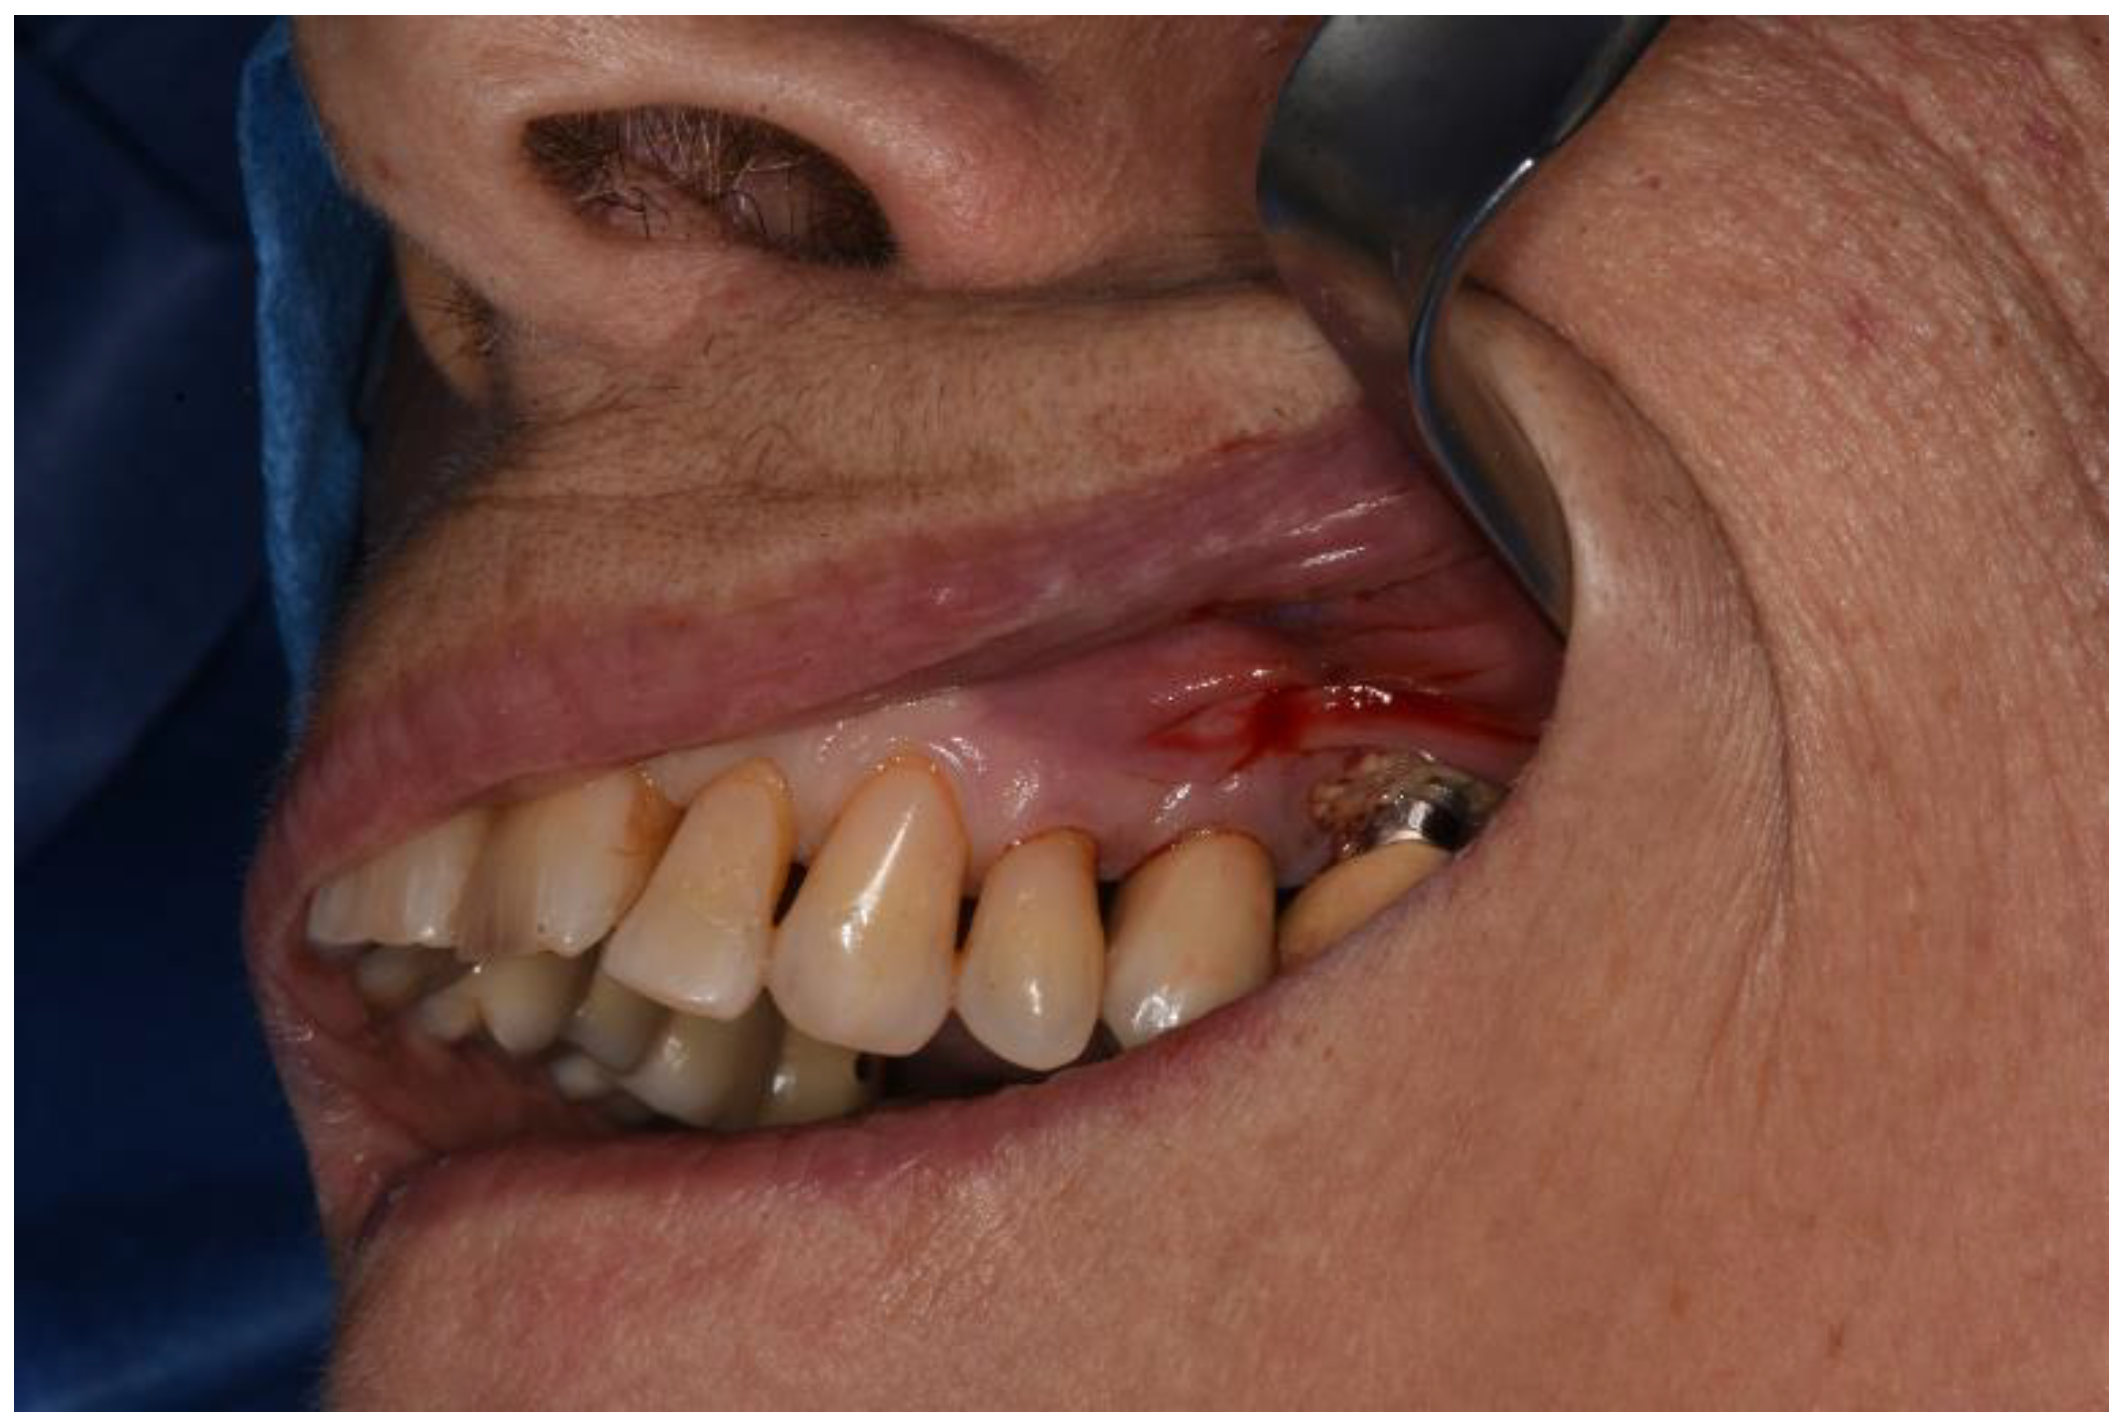

Figure 11. Clinical view at one year follow up.